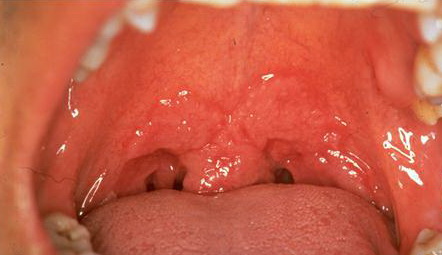

Secondary syphilis = الافرنجي الثانوي